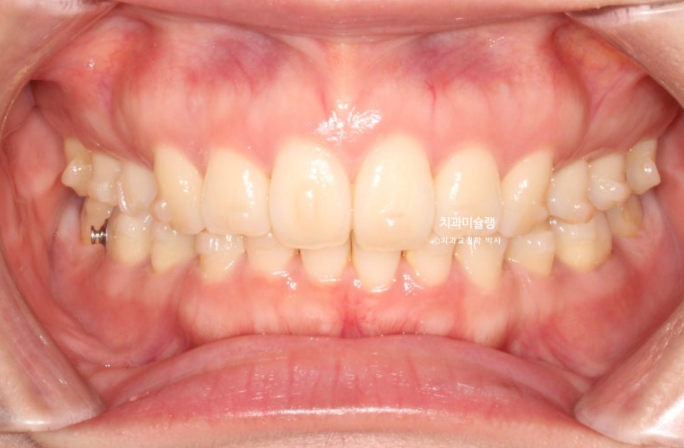

26.01

이제 전후 비교 보겠습니다.

총 치료기간은 3년 2개월, 재제작은 3회 했습니다.

어금니 교합은 뜨는 곳 없이 좋습니다.